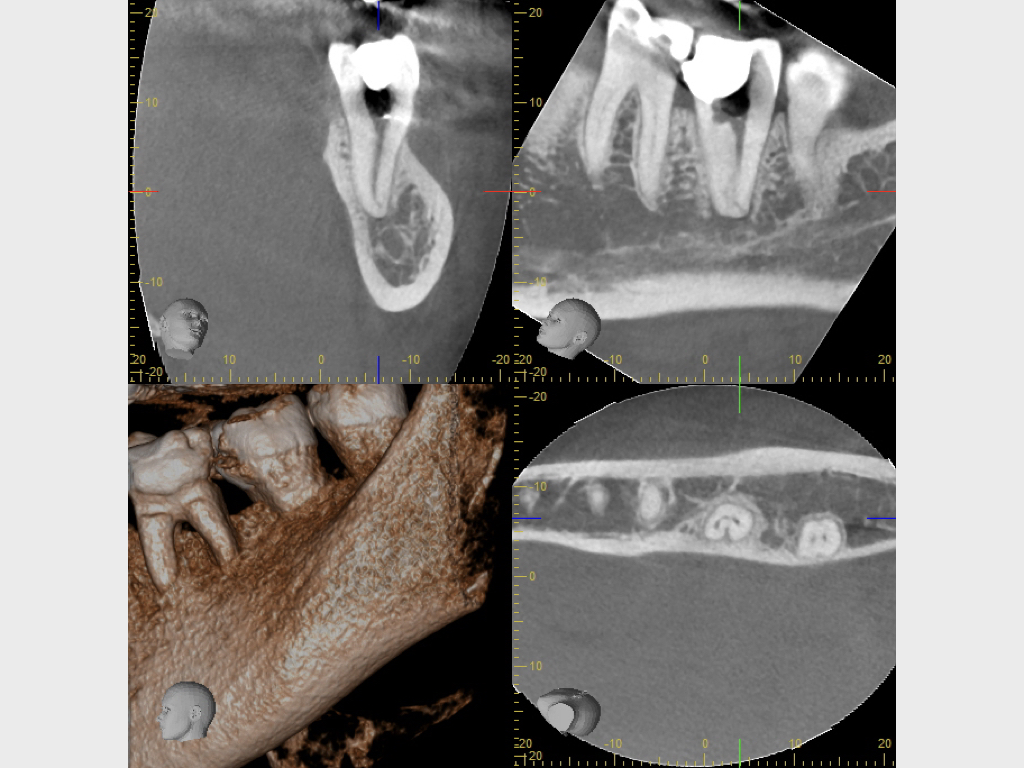

Csh.003

1024 × 768

37 mit akuten Beschwerden